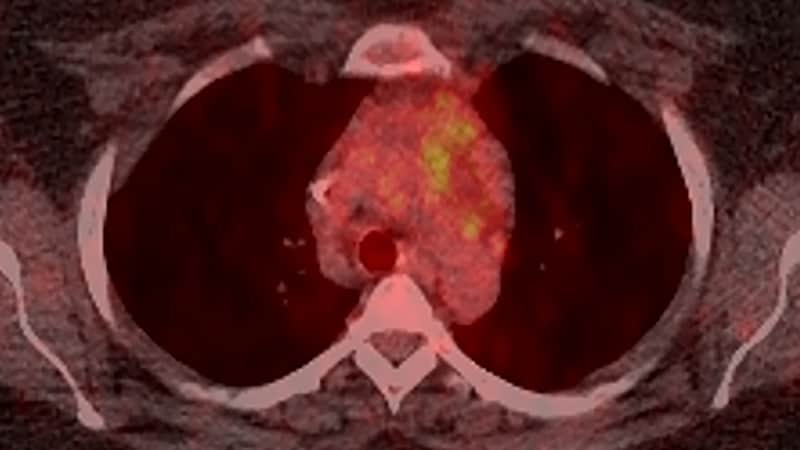

Hodgkin Lymphoma

- Thoracic Hodgkin Disease Imaging